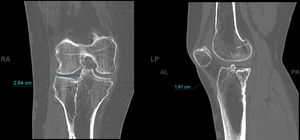

Deviation in millimetres of the load axis relative to the contralateral limb, the medial proximal tibial angle (MPTA) of both limbs, and the difference in degrees between them were analysed using telemetry (Fig. 2).

In the CT study, volumetric acquisition was performed using a multi-slice scanner at .6mm thickness, followed by multiplanar reconstruction at 1.5mm slice intervals. In coronal plane reconstruction, the point of greatest fracture depression in millimetres, corresponding to the maximum joint step, and the maximum width/transverse diameter in millimetres were analysed. In the sagittal plane, the maximum anteroposterior joint step diameter in millimetres and the maximum external tibial plateau slope in degrees were measured (Fig. 3). Post-processing in the axial plane involved delimiting the fracture contour and calculating the affected area in cm2, as well as determining the maximum anteroposterior and transverse diameters in mm (Fig. 4).